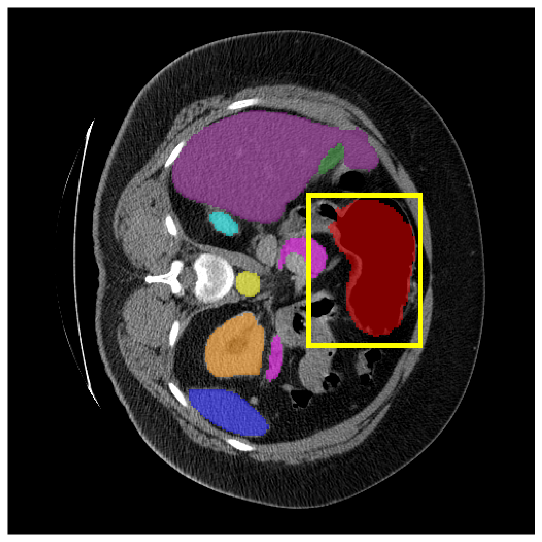

4.3.2 Visual Comparisons

Visualization of our method on the Synapse and ACDC datasets is shown in Fig. 3(a) and Fig. 3(b). For the Synapse dataset illustrated in Fig. 3(a), FCT failed to accurately segment SM and GB, while MERIT achieved precise segmentation of SM but struggled with GB. In contrast, our method achieved accurate segmentation of both SM and GB. Regarding the ACDC dataset shown in Fig. 3(b), while previous methods achieve comparable segmentation of the Myo and LV to the GT, they exhibit noticeable errors on the RV, including invasion into adjacent organs and misrecognition. On the other hand, our method accurately segments across all three structures Myo, LV, and RV, performing as precisely as the GT. We demonstrate the superiority of our method quantitatively and qualitatively.